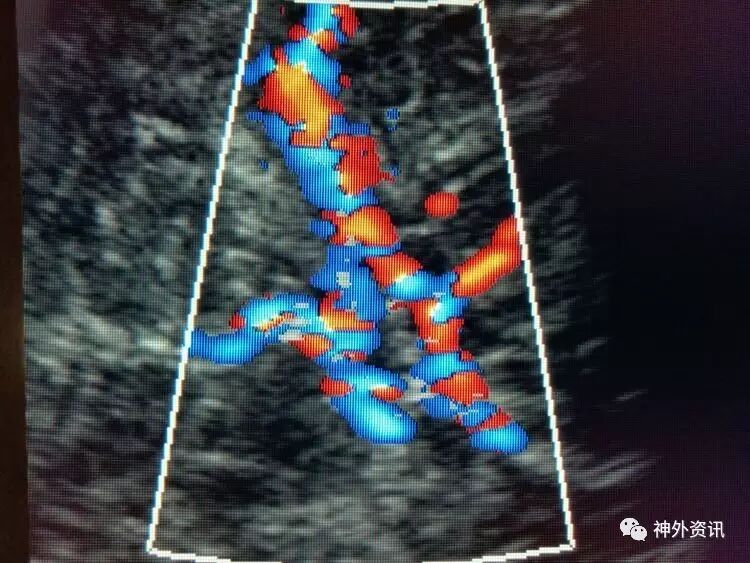

脑血流良好: